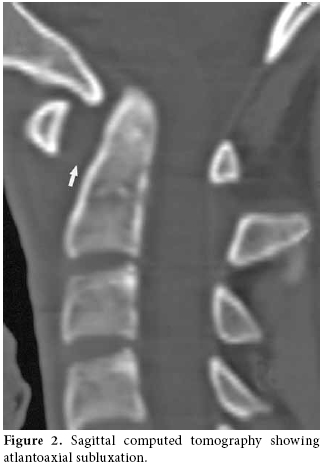

The lateral view of the cervical radiography revealed atlantoaxial subluxation (figure 1). On the computed tomography (CT), the distance between the axis and dens clearly widened as it measured approximately 10 mm (figure 2). The T1-weighted magnetic resonance imaging (MRI) showed a widened atlantodental space (figure 3a). At this localization, T2-weighted images revealed a heterogeneous hyperintense lesion, and at C2, C3, and C4 levels increased retropharyngeal soft tissue thickness appeared (figure 3b). In postcontrast T1-weighted sequences, the increased retropharyngeal soft tissue thickness and lesion showed heterogenous enhancement which was interpreted as soft tissue infection and abscess, respectively (figure 3c).

Radiological investigation plays an important role in the diagnosis. Plain anteroposterior and lateral radiographs may show asymmetry of the facet joints and increased predental space.[8] Both CT scanning and MRI are diagnostically used.[10] In our case, retropharyngeal soft tissue swelling was demonstrated. Dynamic studies may be necessary, but they may cause neurological complications.[14]